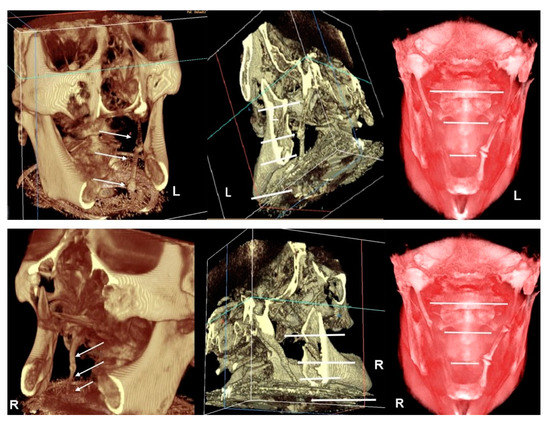

Apart from these findings, there were multiple astonishing CBCT images of the different planes, which show an impressive bilateral mineralization of the styloid complex. All the taken CBCT radiographic images showed a “collar-like” multi-interrupted and segmented calcified stylohyoid complex (SHC). On the left side, the segmented calcified styloid ligaments fully stretched to the lesser cornu of the hyoid bone and on sagittal CBCT images, measuring 85.87 mm in length with an average width of 3.63 mm, while the right side barely reached the lesser horns of the hyoid bone, measuring 81.13 mm in length with an average width of 2.58 mm (Figure 5).

Figure 5. Top image–CBCT three-dimensional reconstruction shows an impressive calcification of the SHC in different image modes (left–default 2 mode, center–default mode, right-skin/red mode throughout antero-posterior slice sectioning). On the left side, the CBCT radiographic appearance of a “collar-like” and elongated SHC shows a multi-interrupted and segmented calcified SHC, fully stretched to the lesser cornu of the hyoid bone (see arrows). Bottom image–in a different image mode, on the right side, CBCT three-dimensional reconstruction shows the segmented calcified SHC which barely reaches the lesser cornu of the hyoid bone (left–default 2 mode, center–default mode, right–skin/red mode throughout antero-posterior slice sectioning) (see arrows).